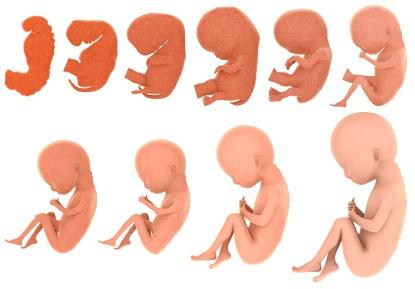

A restrição de crescimento intra-uterino é definida como uma falha do feto em atingir o peso para que foi geneticamente…